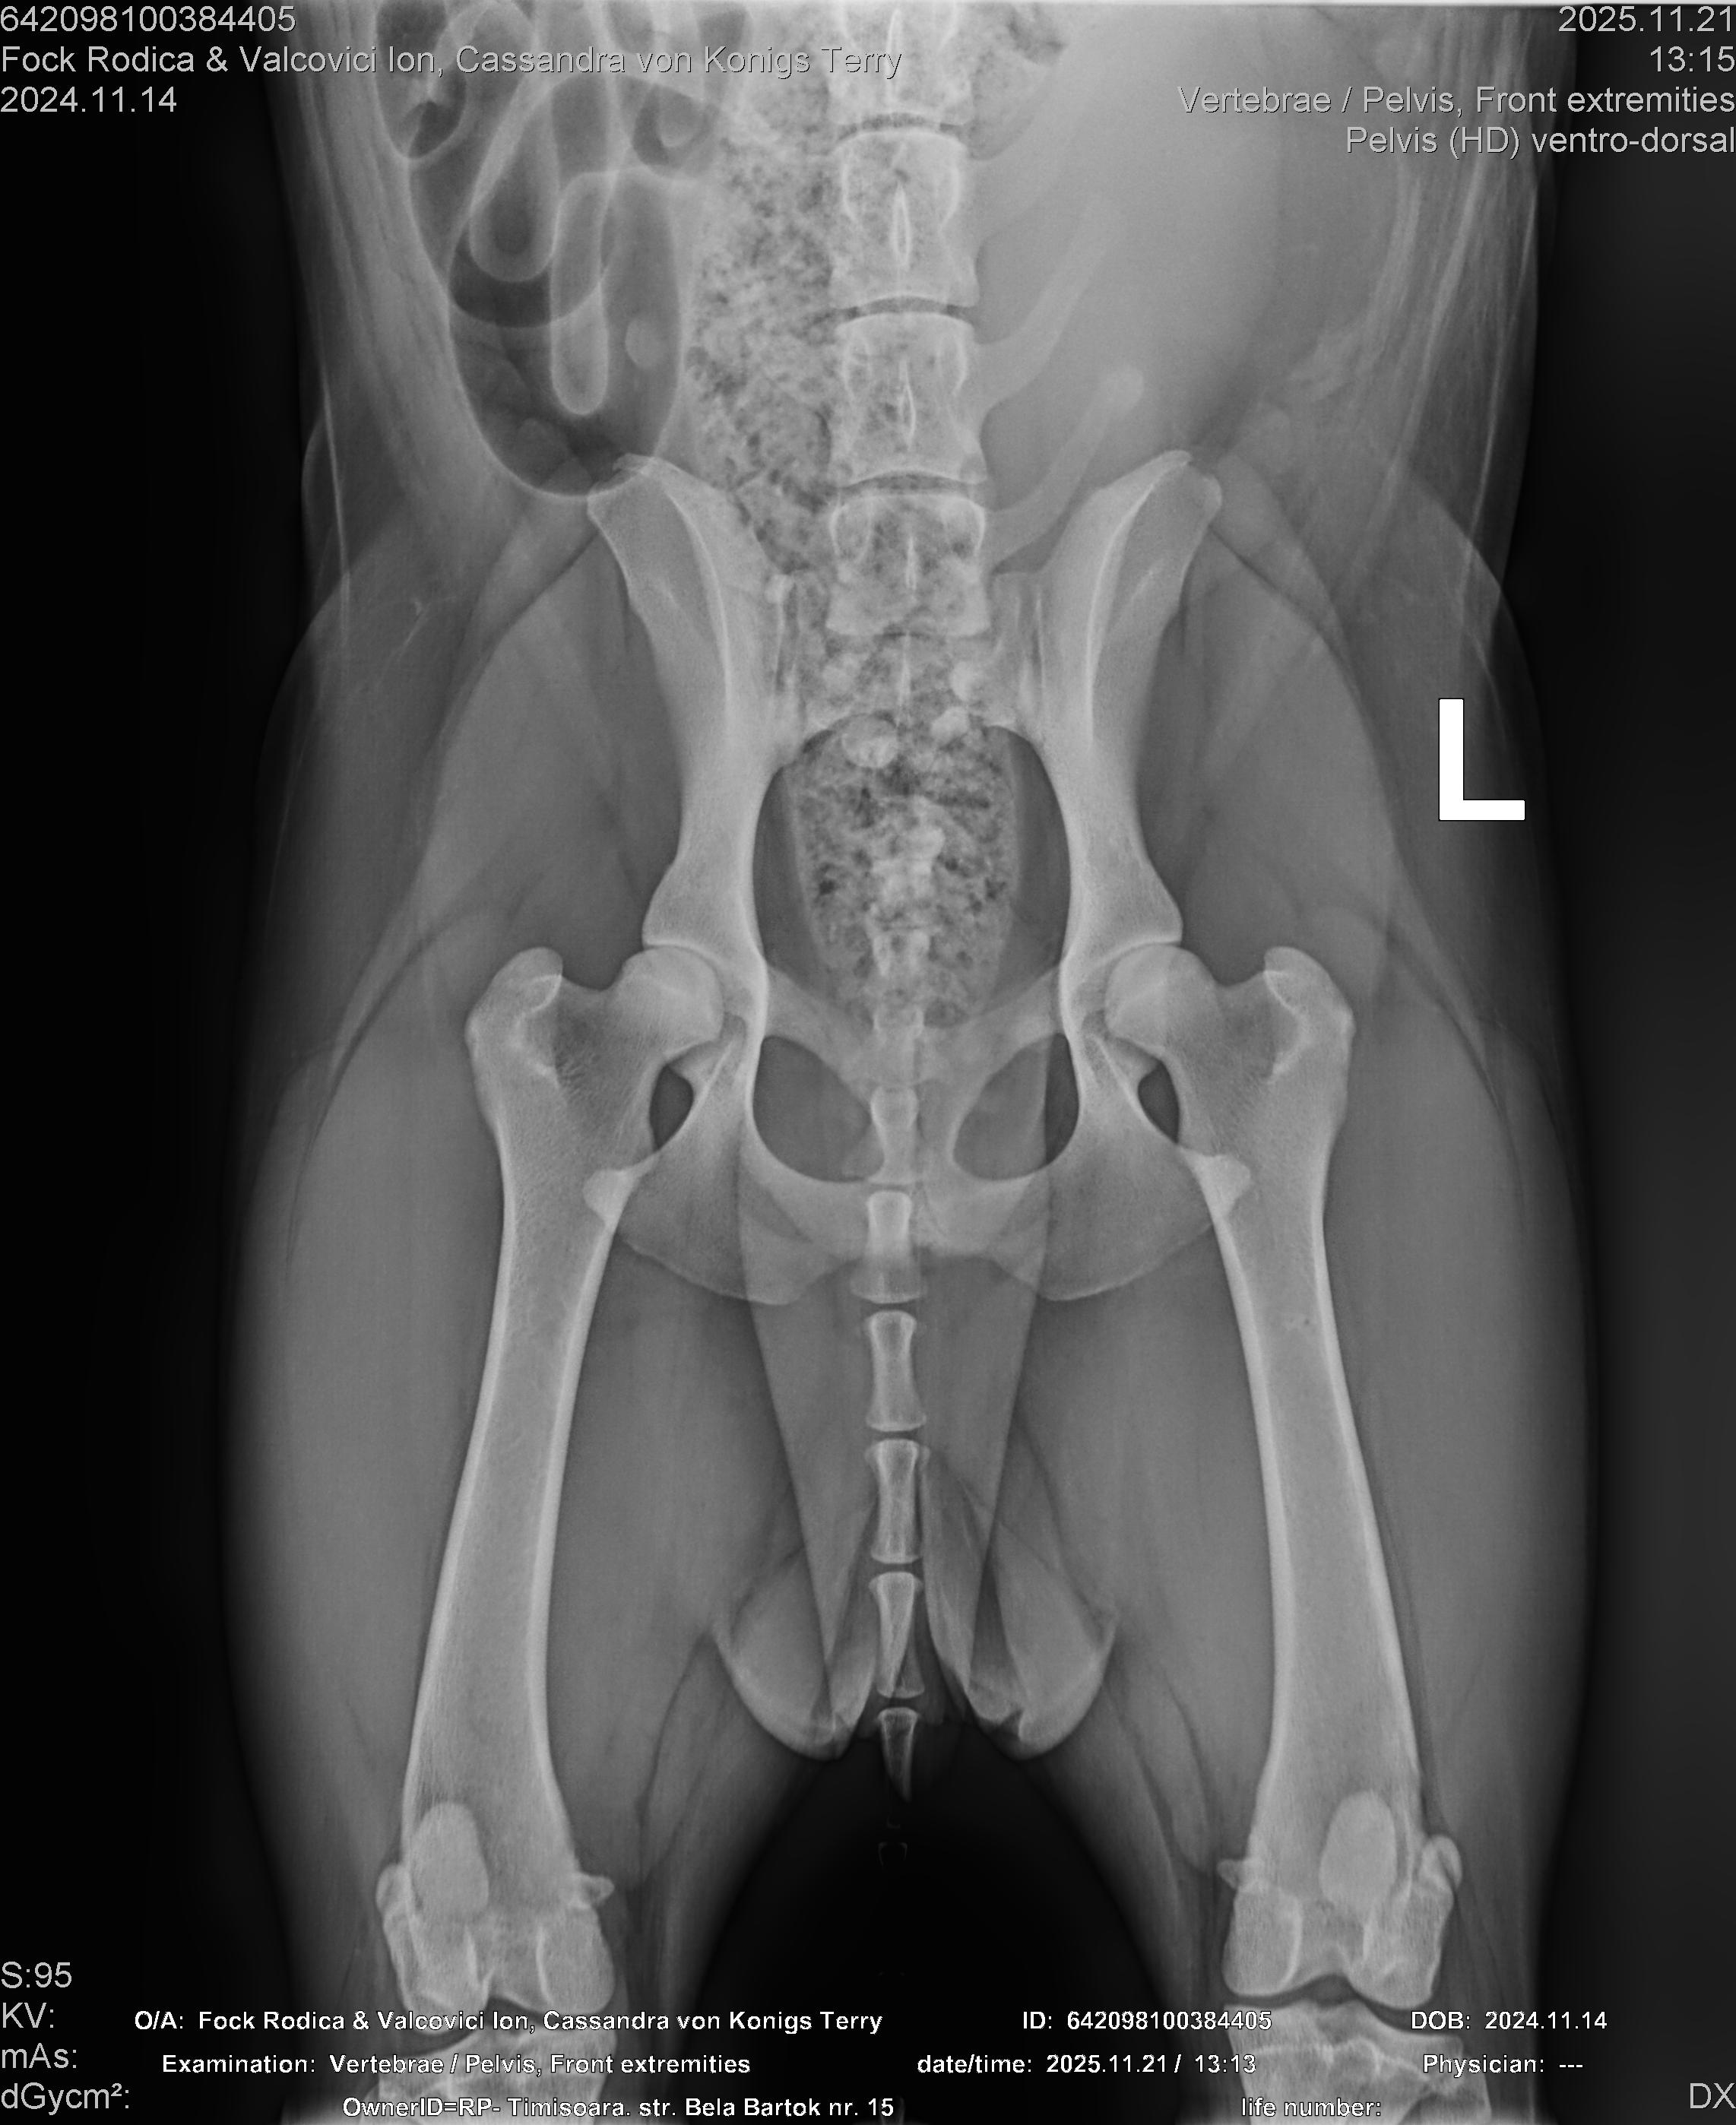

CASSANDRA VON KONIGS-TERRY

( CASSY )

Data nasterii:

14.11.2024

Crescator:

FOCK RODICA si VALCOVICI ION